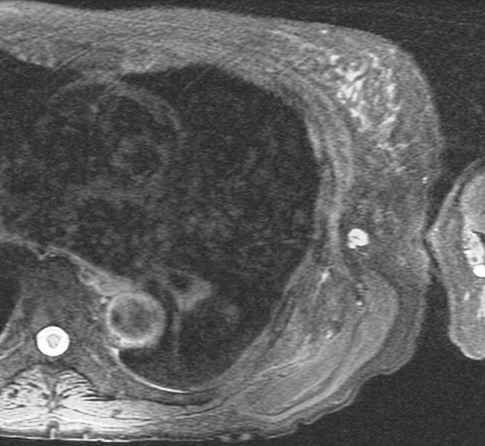

70 yo with 3 year history of slow growing mass in scapular region.

Typical location and dark appearance of this psuedotumor. Reference article.

Elastofibroma dorsi